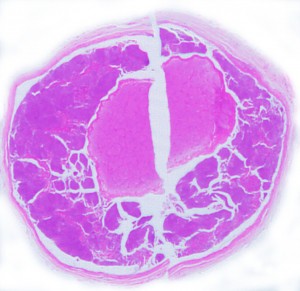

比較的急速に視力低下して手術摘出した例

右目が暗いという症状で発症して,眼科では視神経乳頭腫脹とわずかな視野欠損だけで発症した患者さんです。3年間観察されましたが,その間には眼底所見も視力 Vd 1.2 も変化がなかったとの眼科からの報告です。そのすぐ後で患者さん本人は,右目が暗くなる回数が増え、視野狭窄があり軽い眼球突出,まわりがぼやけてますが中心は1.0見える状態との訴えで相談を受けました。主治医の先生の方針では経過観察ということで,まだ視力も良いので私もそうした方がよいと同意したのですが,その後半年くらいで視力が手動弁まで低下してしまいました。眼球運動と右眼球を温存するために腫瘍を摘出しました。

左側は,摘出標本の輪切りの写真です。この部位は腫瘍の発生した部位ではありません。一番外側にみえるのは視神経鞘 optic sheathという膜です。その内側が髄膜腫で,その内側が視神経です。すなわち髄膜腫は,視神経鞘と視神経の間のくも膜下腔を,這うように伝わって増殖伸展しています。このくも膜下腔には視神経への栄養動脈や網膜動脈も入っているので,この腫瘍だけを視神経や細動脈を傷つけずに摘出することはできないのです。